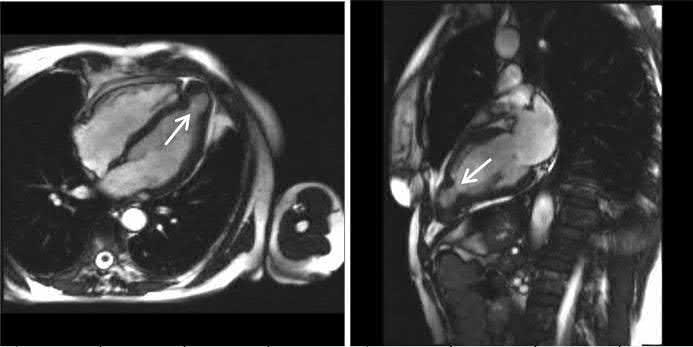

Correct answer: 1

The echocardiogram (of intermediate quality) detected an apical aneurysm. The ventricular aneurysm with a paradoxical expansion during systole and end‐systolic flow pattern from the ventricle to the aneurysm was better demonstrated with CMR (next figure, arrows) (Fiol M, et al. Int J Cardiovasc Imaging. 2015;31: 1261–1262). A “normal variant” is uncommon, but still possible, at the age of 60.

A 68‐year‐old diabetic patient presented with precordial pain radiating to the back. The ECG (Figure) was interpreted as non‐diagnostic.

An aortic CT was performed to rule out aortic dissection.